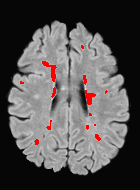

We observed that memberships predicted with an FC layer result in more false positives compared to a fully convolutional network. An example is shown in Fig. 2, where lesion memberships are generated from MPRAGE and FLAIR using the proposed model of convolutional pathways and a comparable model where the last convolutional pathway after concatenation (see Fig. 1) is replaced with a FC layer predicting voxel-wise memberships. The membership image generated with an FC layer, although being close to inside the lesions, has high values () in the left and right frontal cortex where the FLAIR image shows some artifacts. However, the membership obtained with the proposed method shows relatively low values near the frontal cortex.

With FC layer, voxel-wise predictions are performed for each voxel on a new image. Therefore the prediction time for the whole image comprising millions of voxels can take some time even on a GPU, as mentioned in Wachinger et al. (2017). In contrast, with fully convolutional prediction, lesion membership estimation of a mm3 MR volume of size takes only a couple of seconds. Note that although patches are used for training, the final trained model contains only convolution filters and does not depend in any way on the input patch size. Therefore during testing, the lesion membership of a whole 2D slice, irrespective of the slice size, is predicted at a time by applying convolutions on the whole slice. Without an FC layer, the images need not be decomposed into sub-regions, e.g., Kamnitsas et al. (2017). Consequently, there is no need to employ membership smoothing between sub-regions. In addition, since the training memberships, generated by Gaussian blurring of hard segmentations, are smooth, the resultant predicted memberships are also smooth (Fig. 2 last column).